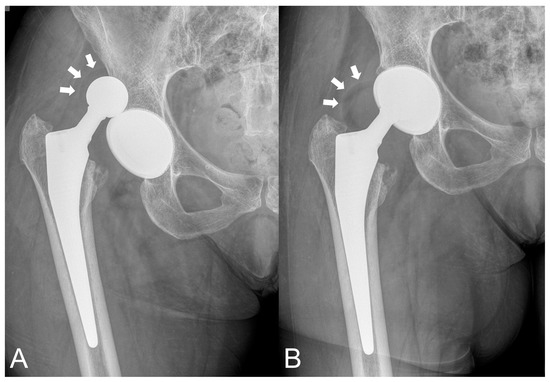

- Chalmers, B.P.; Dubin, J.; Westrich, G.H. Modular dual-mobility liner malseating: A radiographic analysis. Arthroplast. Today 2020, 6, 699–703. [Google Scholar] [CrossRef]

- Romero, J.; Wach, A.; Silberberg, S.; Chiu, Y.F.; Westrich, G.; Wright, T.M.; Padgett, D.E. 2020 Otto Aufranc Award: Malseating of modular dual mobility liners. Bone Joint J. 2020, 102 (Suppl. S7), 20–26. [Google Scholar] [CrossRef]